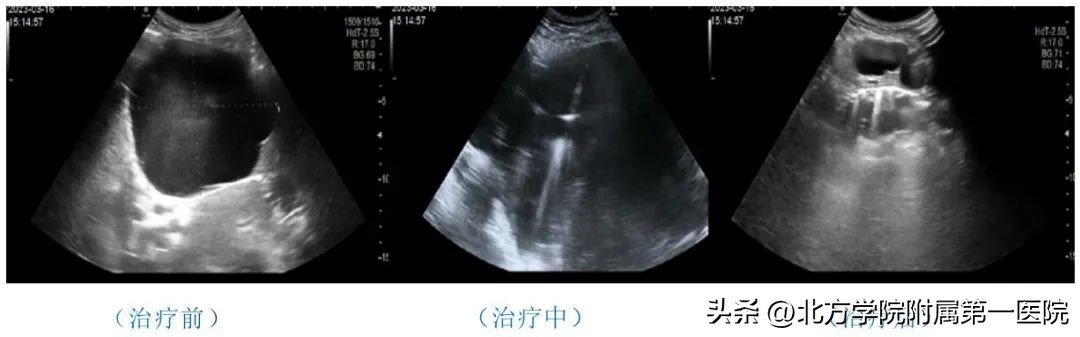

3月16日下午,我院超声科开展超声引导下经皮肝囊肿穿刺硬化治疗。该治疗技术全程在超声实时监测下进行,操作安全,精准度高,创伤小,价格低,局部麻醉,患者全程无任何不适,短时间内有效解除了患者病痛,赢得了患者赞誉。

此例患者来自肝胆外科,是一位高龄的多囊肝患者,较大的囊肿已达到直径约11cm,囊肿下缘接近脐水平,腹部隆起明显,严重压迫了周围组织结构,引起了上腹部不适症状。因为患者年龄较大且合并有高血压、冠心病等病史,不能耐受手术治疗,所以超声医学科为其进行了超声引导下肝囊肿硬化治疗。

超声引导下囊肿硬化治疗术是在超声实时监测下,通过短时间抽出囊液,反复冲洗囊腔后注入硬化剂,使囊壁内皮细胞不再分泌液体,达到治疗目的。这种疗法准确性高、创伤小、手术时间短,能有效减轻患者痛苦。